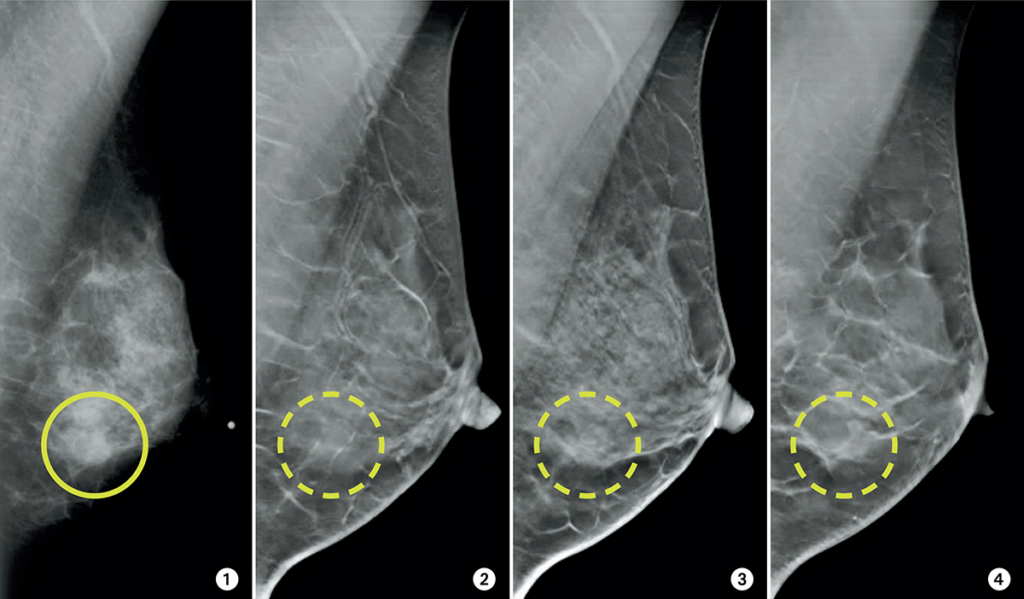

ماموگرافی سه بعدی در برخی زنان دقت بالاتری دارد، به ویژه در پستان های متراکم.